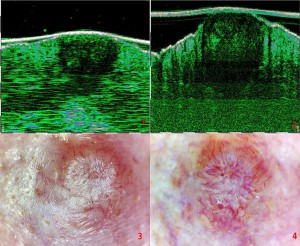

-Υπέρηχος Υψηλής Συχνότητας (HFUS) και Ιστολογία

-Διαφοροποίηση τύπων βασικοκυτταρικού καρκινώματος